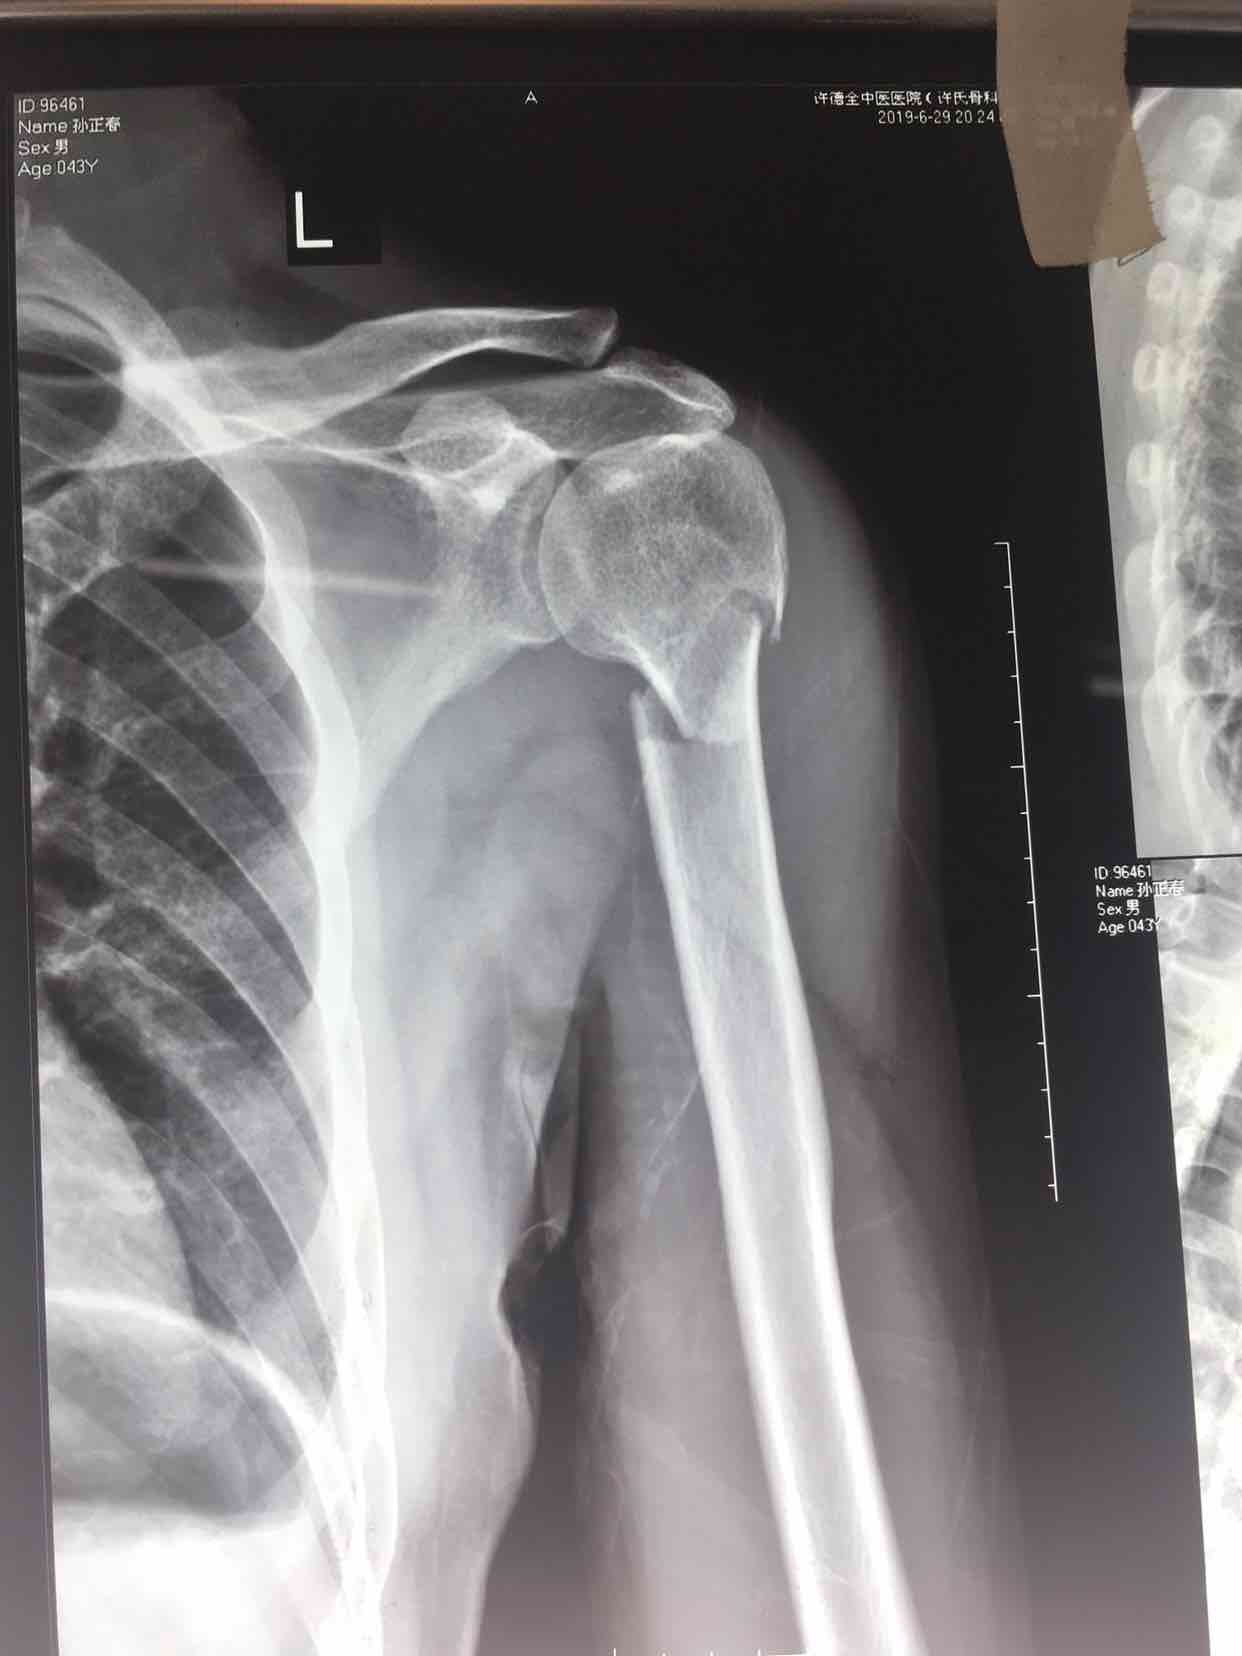

骨折 肱骨外科颈骨折

摔伤后左上臂肿痛,活动受限1小时入院。既往身体健康,无特殊不良嗜好。

生命体征平稳,心肺复未见异常。左上臂肿胀,畸形,局部皮色皮温正常,压痛及纵向叩击痛阳性,可及骨檫音或骨檫感,活动受限,末梢血运感觉正常。

诊断肱骨外科颈骨折在臂丛麻醉下行切复内固定术,术后抗炎,消肿止痛等处理。